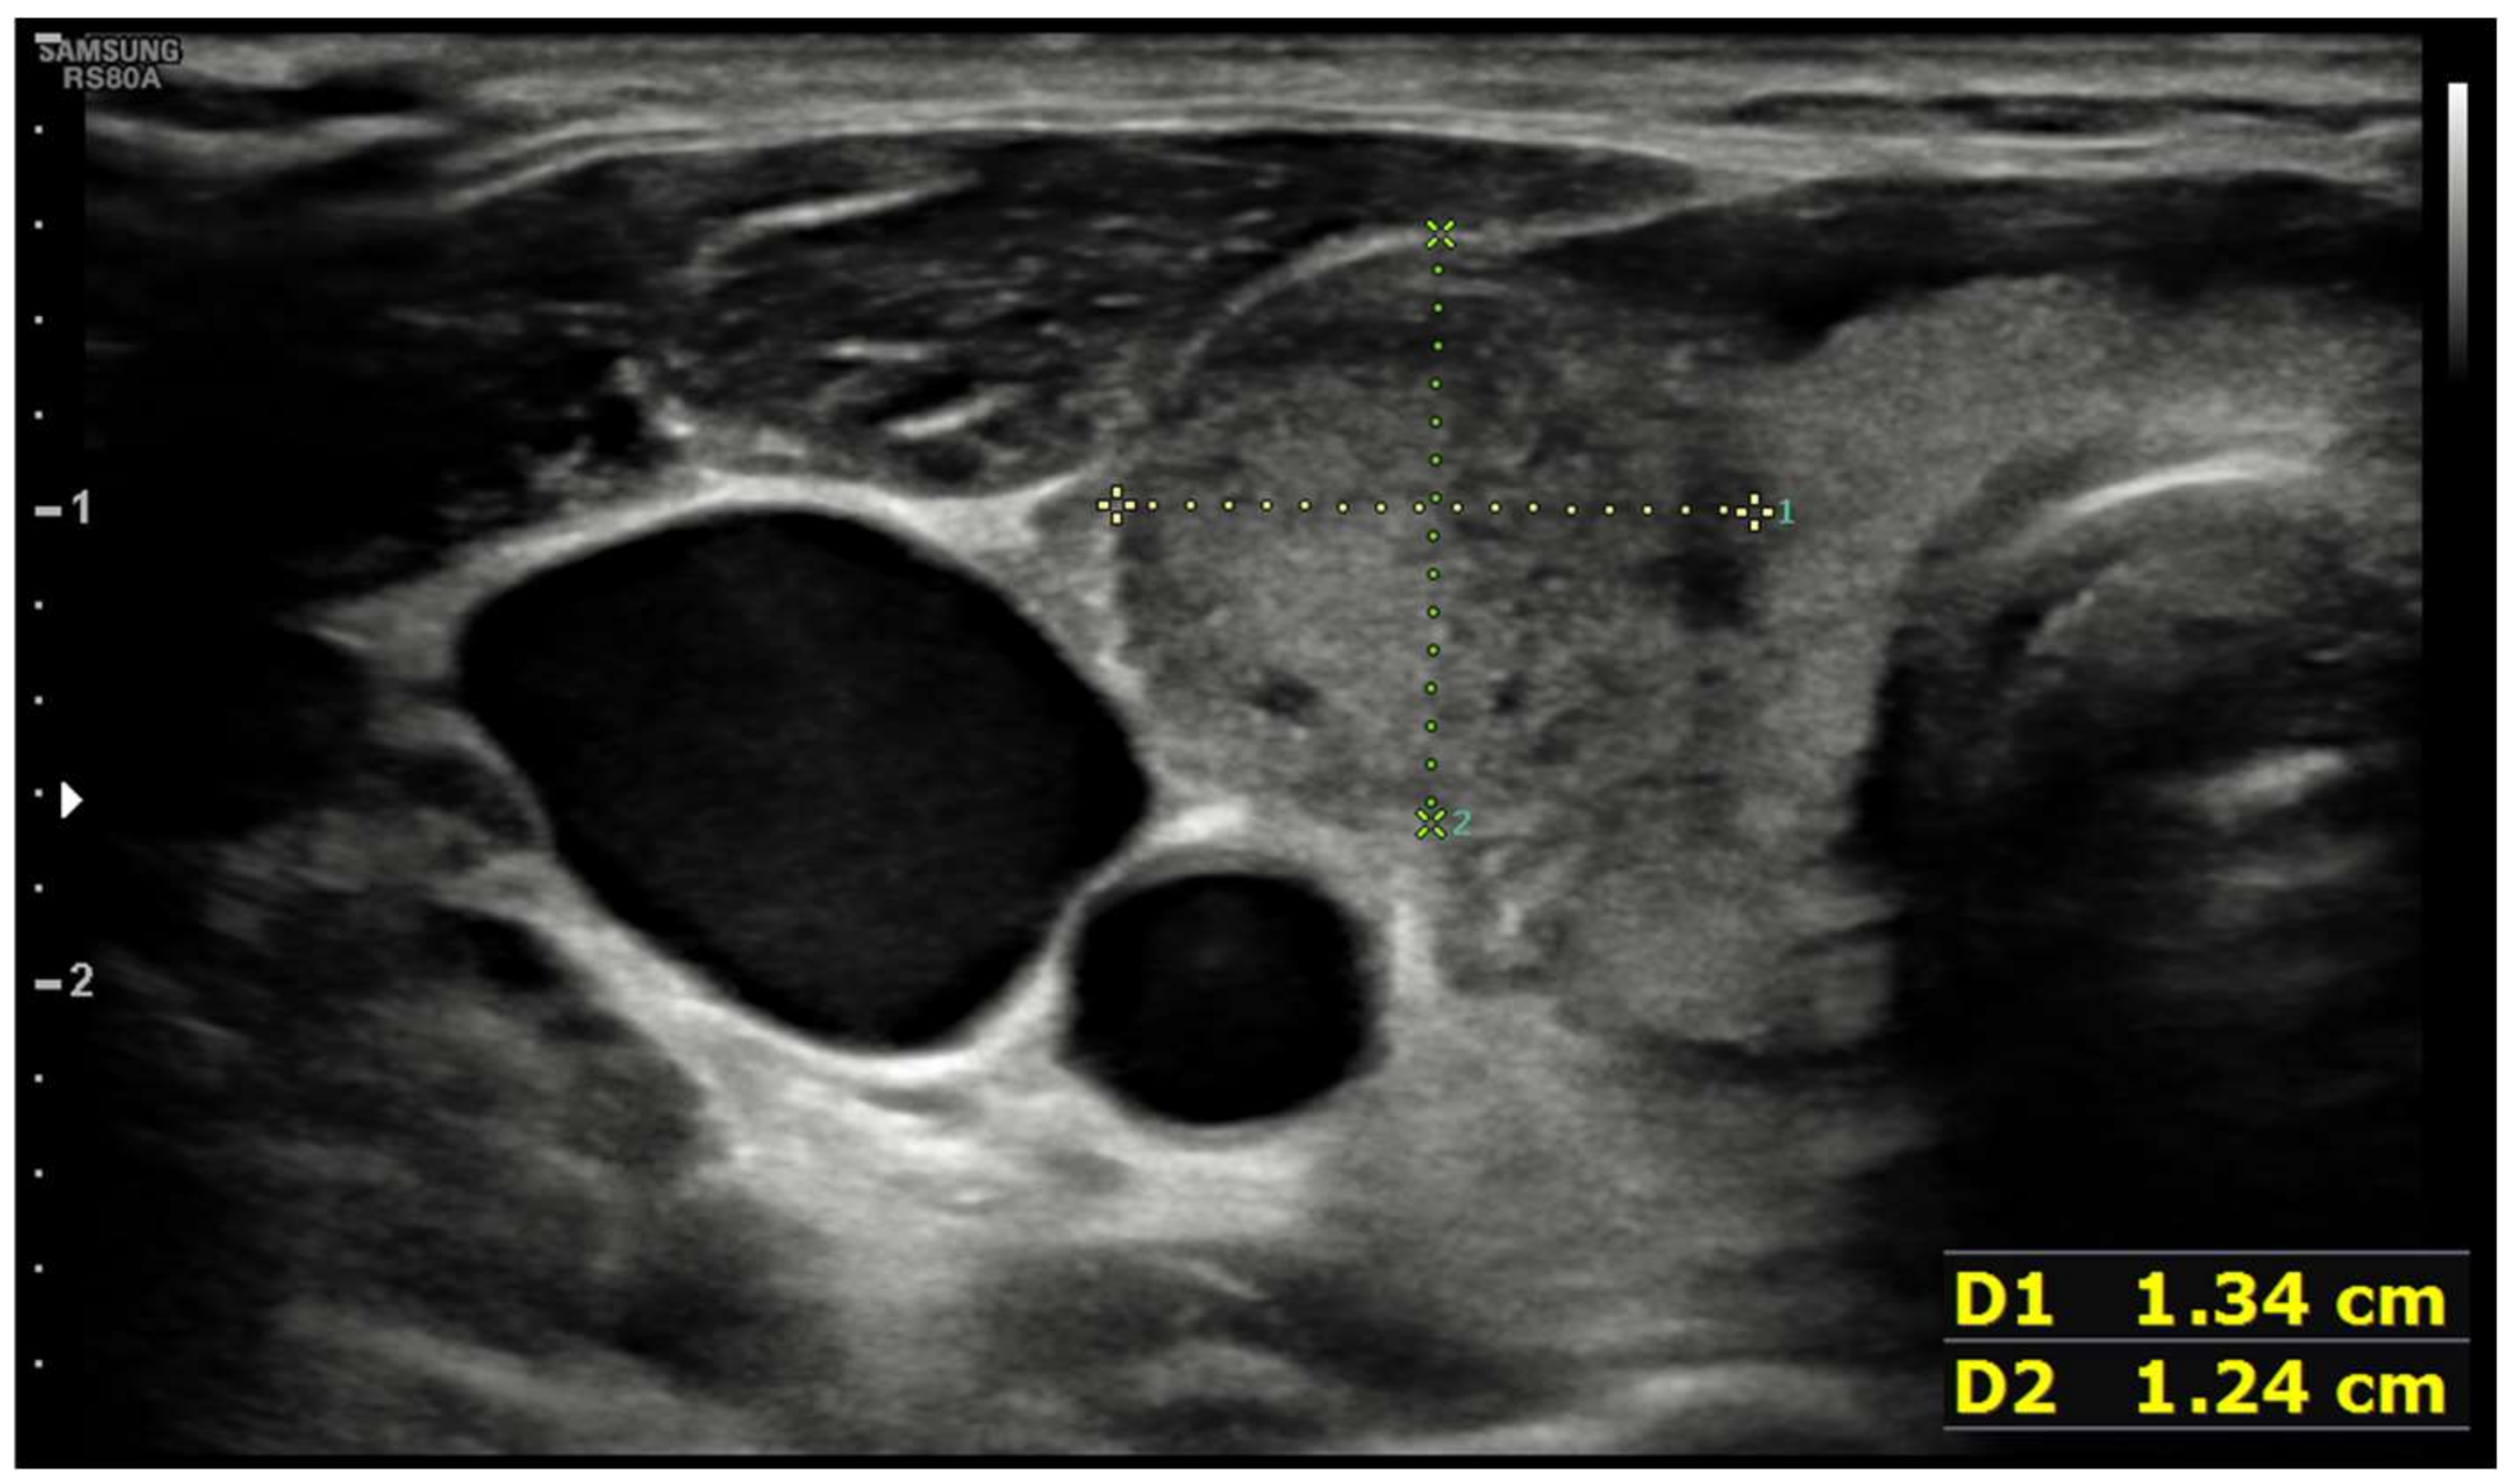

| Ultrasound findings at presentation | Asymmetric thyroid enlargement with two hypoechoic areas with no internal vascularity on right thyroid lobe | Diffuse thyroid enlargement with hypoechoic areas with heterogeneous echotexture and no evidence of increased vascularity | Diffuse enlargement of thyroid gland with hypoechoic nodules with hyperechoic shoots (micronodular pattern) without increase in vascularity | ||||||||||||||